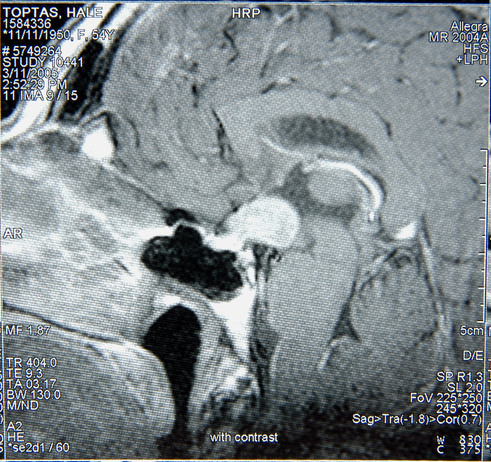

Bulgular: Fizik muayenesinde; TA: 120/80mm/Hg, NB: 88 atım/dk, yuzunde rozasea mevcuttu, sistem muayenesi doğaldı. Laboratuvar analizinde; TSH:1,2mU/L(0,55-4-78), sT3:3,24ng/L (2,3-4,2), sT4:1,26ng/dl(0,89-1,76), Hb:12g/dL(12-15,6), ferritin:6 mikrogram/L(10-291), aTG:269,9IU/mL(<1,3), aTPO:389U/mL(<60), glukoz:86mg/dl(70-99) idi. Hasta levotiroksin 100mcg tedavisi alıyordu. Klinik takibinde taşikardisi nedeni ile ilac dozu duşuruldu, demir eksikliği anemisi nedeni ile replasman tedavisi aldı. Taşikardisi nedeni ile kardiyoloji bolumune yonlendirilen hastaya ekokardiyografi(EKO) planlandığı ancak hastanın yaptırmadığı oğrenildi. Aclık ve tokluk hipoglisemileri olan hastaya mixed meal testi yapıldı, test sırasında hipoglisemik değeri olmadı, uzamış aclık testi planlandı ancak yatış kabul etmedi. Pankreas MR’ında, sol atrium icerisinde 38x36mm boyutlarında T1A’de hipo, T2AG’de hiperintens, IVKM enjeksiyonu sonrası yapılan dinamik incelemede kontrastlanmayan lezyon goruldu. Pankreas parankim intensitesi homojen olduğu saptandı, belirgin kitle lezyonu gorulmedi. EKO’sunda ejeksiyon fraksiyonu: %60, sol atrium icerisinde 4,3x3,3cm, duzgun sınırlı yuvarlak şekilde, interatrial septuma sap ile tutunan ve septumu sağa deviye eden icerde yer yer kalsifikasyon odakları iceren miksoma uyumlu kitle izlendi. Hasta sol atriyal kitle nedeniyle opere oldu. Patoloji sonucu kardiyak miksoma ile uyumlu geldi. Hastanın Karney kompleksi acısından tetkiklerinde; 1mg DST kortizol baskılı, Glukoz-GH supresyon testi GH <0,05μg/L, genetik test calışılamadı.